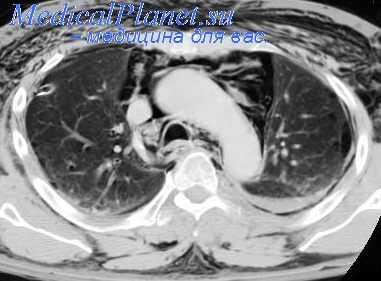

Огромных размеров патологическое образование, оттесняющее аорту впереди в сторону сердца, занимающее практически всю левую половину грудной полости, оттесняющее селезенку, почку и диафрагму вниз. Это злокачественная нейрогенная опухоль. Но сказать о том, что эта опухоль исходит из нервных образований, при томографическом исследовании очень сложно и не всегда возможно.

Почему мы не можем сегодня ограничиваться только этими данными, только локализацией. Конечно, возможные ошибки. Различные опухоли могут располагаться в одном и том же отделе средостения. Мы это видели на примере средней части переднего средостения.